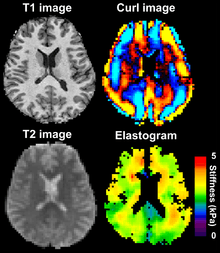

Magnetic resonance elastography works by using an additional gradient waveform in the pulse sequence to sensitize the MRI scan to shear waves in the tissue. The shear waves are generated by an electro-mechanical transducer on the surface of the skin. Both the mechanical excitation and the motion sensitizing gradient are at the same frequency. This encodes the amplitude of the shear wave in the tissue in the phase of the MRI image. An algorithm can be used to extract a quantitative measure of tissue stiffness from the MRI in an elastogram.